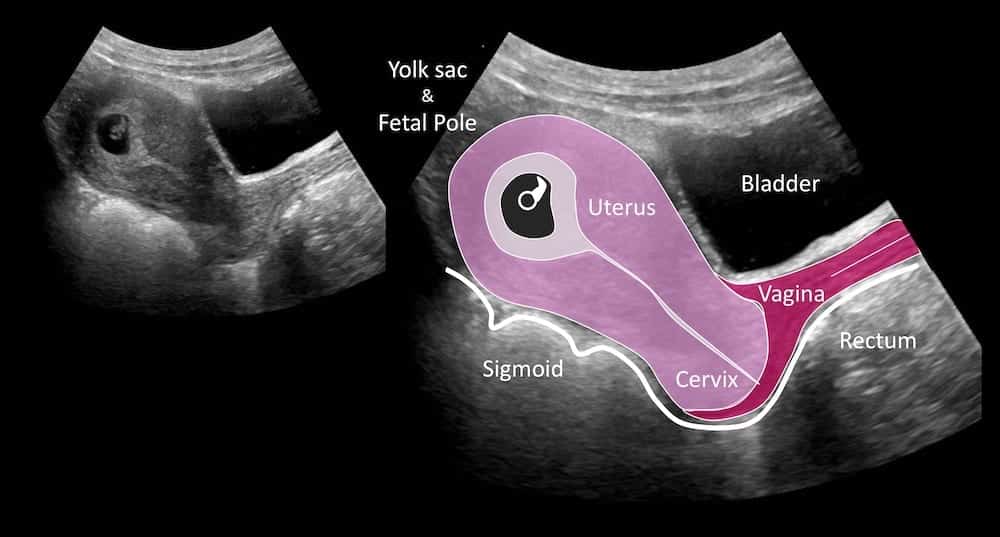

Ultrasound Case 046 LITFL POCUS Self Assessment Quiz

https://litfl.com/wp-content/uploads/2018/12/LITFL-Top-100-Ultrasound-46-02-6-weeks-pregnant.jpg